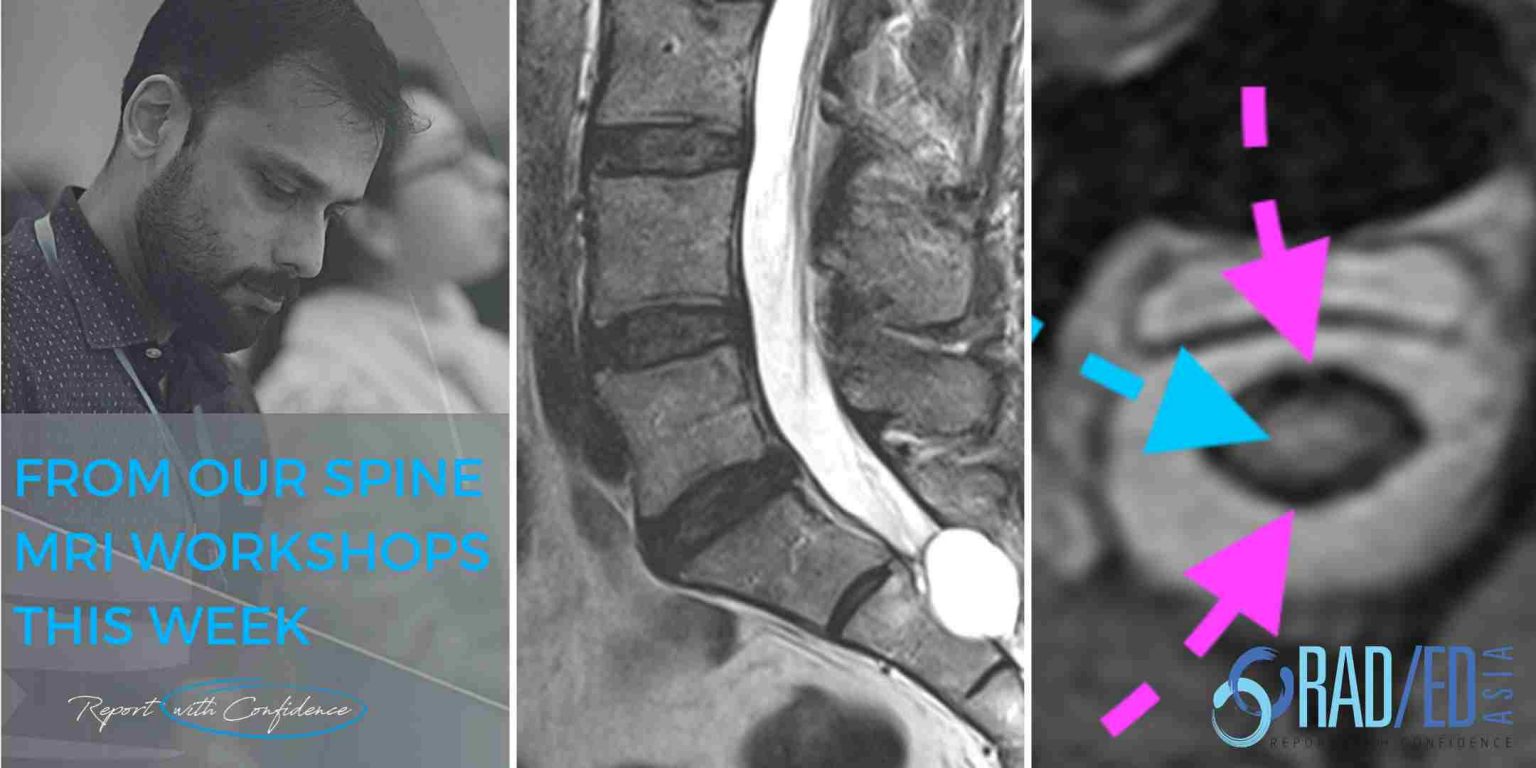

From radedasia.com

SPINE MRI ONLINE RADIOLOGY COURSE NERVE ROOTS KEY POINTS FROM OUR Facet Joint Vs Nerve Root the specific symptoms depend on where the affected joint is located and what nerve roots it affects. however, the joint can become enlarged, like any other joint that has arthritis, and press on nerve roots that could cause pain to radiate down your. most people with facet joint syndrome experience pain in the lower back due to. Facet Joint Vs Nerve Root.